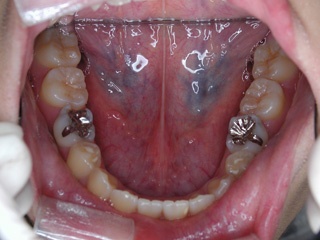

診断名:下顎左右第二小臼歯先天欠如、下顎左方偏位を伴う下顎前突

抜歯/非抜歯および抜歯部位:抜歯(下顎左右第二乳臼歯)

下顎の第二小臼歯の先天欠如が見られました。先天性欠如歯がある場合、上下顎小臼歯抜歯のスタイルで歯数を合わせる事も多いのですが、抜歯数が増えるのが難点です。 プロファイル、下顎前突、非対称の問題を考慮して下顎にオーソアンカー SMAPシステム を植立し、下顎晩期残存の乳歯のみを抜歯し、永久歯の抜歯は行わず空隙を閉鎖致しました。大臼歯の咬合についてはIII 級仕上げ という噛み合わせにしています。